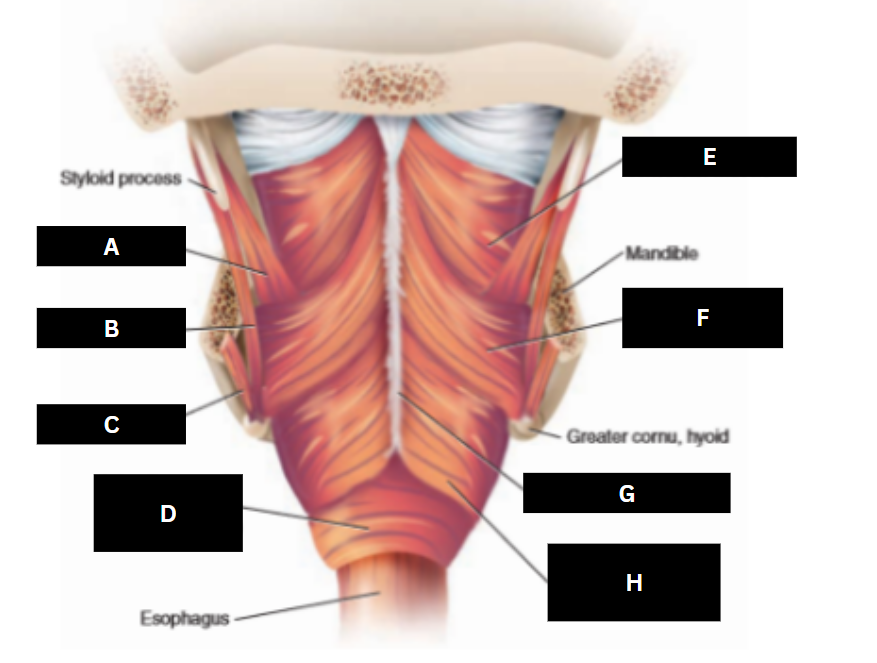

Stylopharyngeus

A

Styloglossus

B

Stylohyoid

C

Cricopharyngeus

D

Superior pharyngeal constrictor

E

Middle pharyngeal constrictor

F

Pharyngeal raphe

G

Inferior pharyngeal constrictor

H